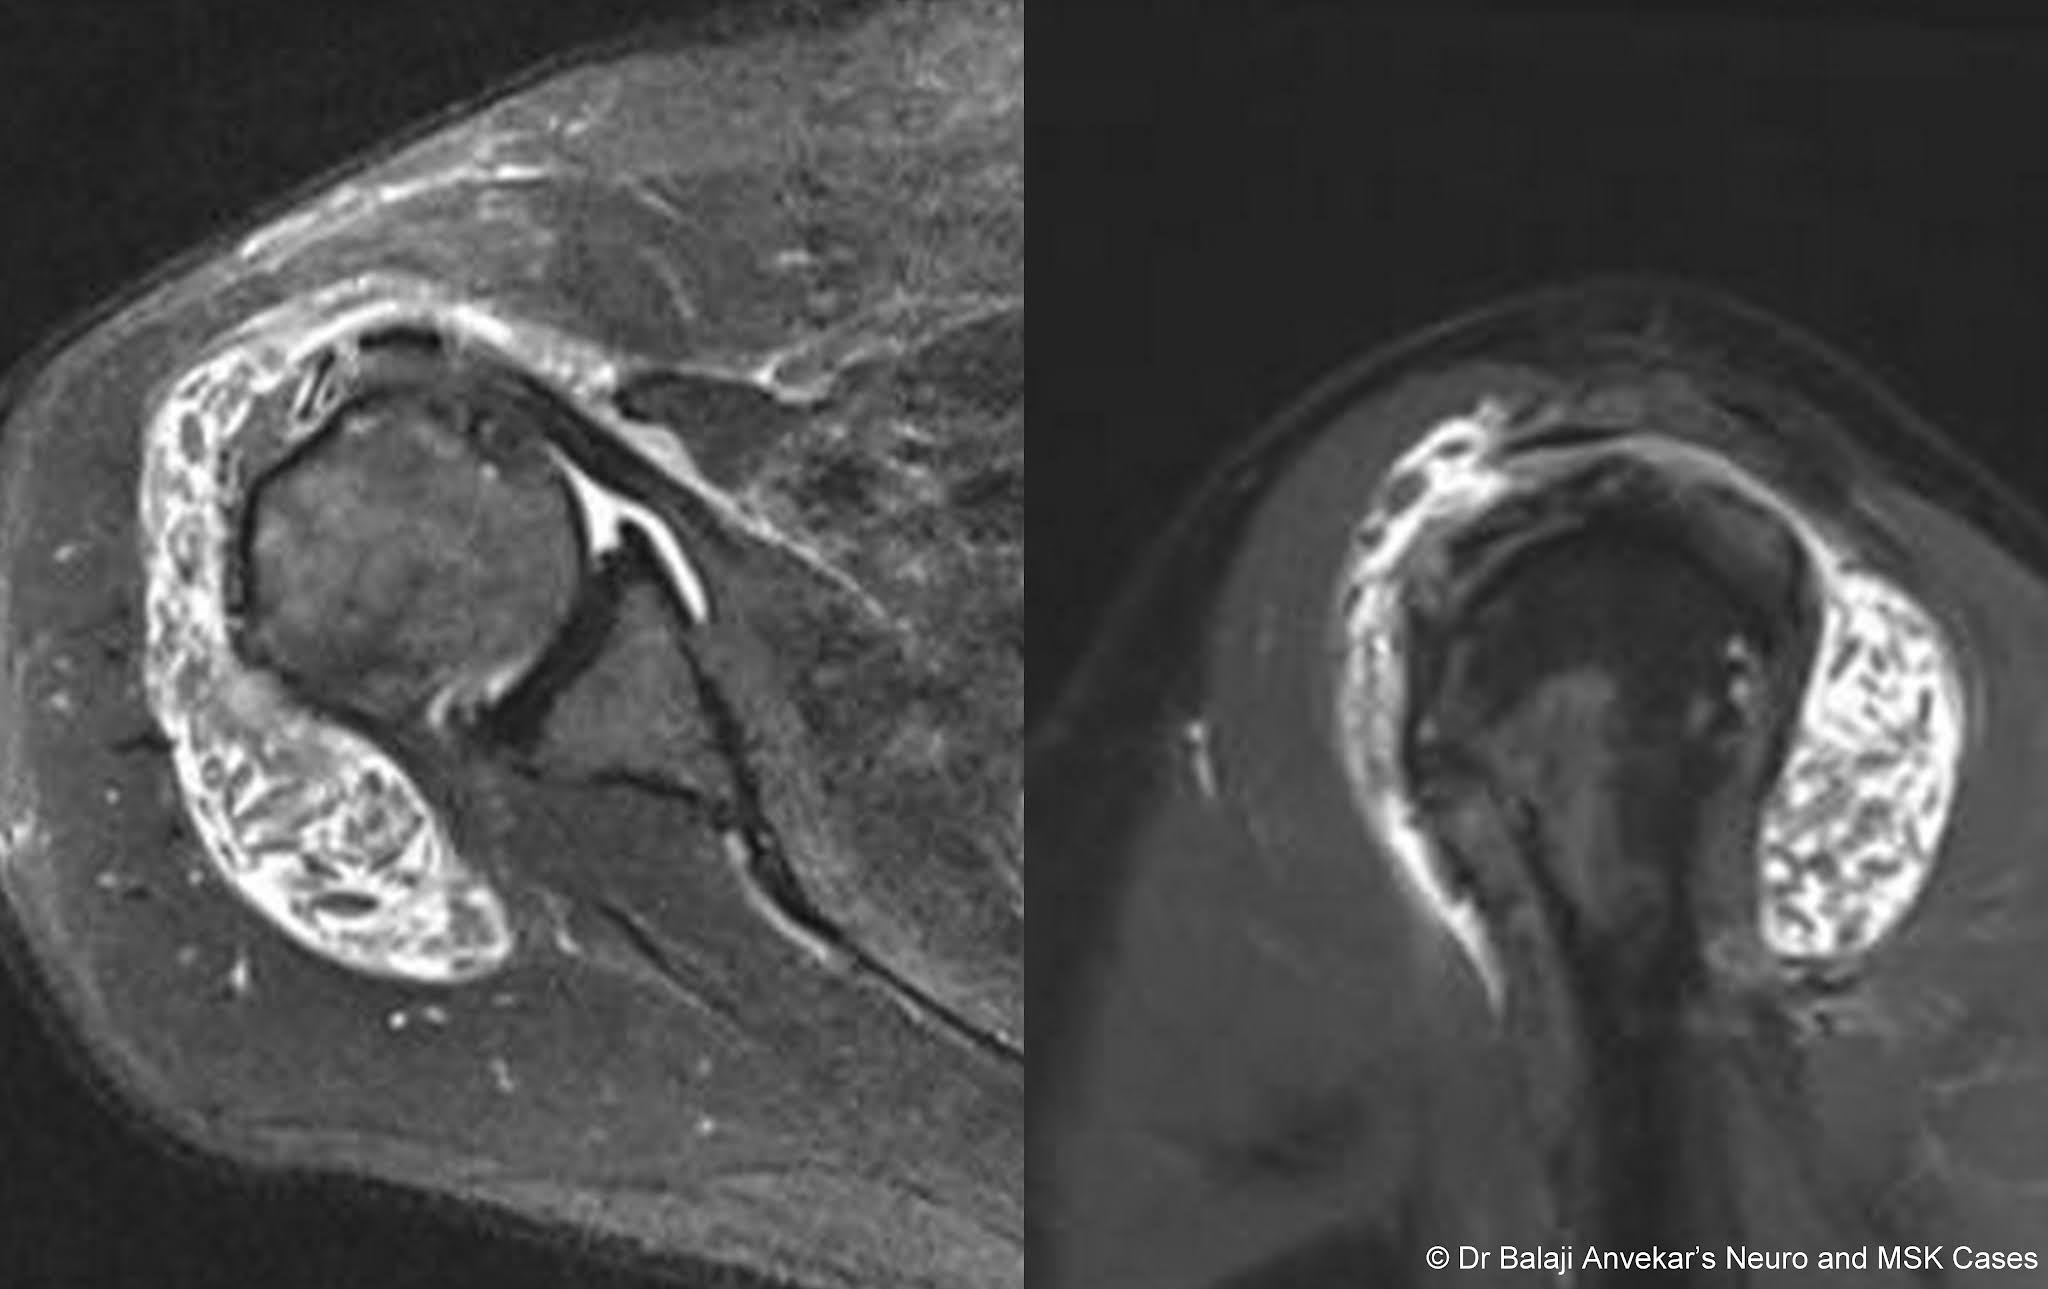

From www.neuroradiologycases.com

Dr Balaji Anvekar FRCR Rice bodies in subdeltoid bursa MRI Shoulder Bursa Mri the subcoracoid bursa is located anterior to subscapularis and beneath the coracoid process and extends caudal to the conjoined tendons. mri of the shoulder continues to evolve but remains integral for evaluating patients with. mr is the best imaging modality to examen patients with shoulder pain and instability. We describe the mr anatomy of the subcoracoid bursa. Shoulder Bursa Mri.